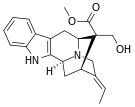

Morphinans

Morphinan series

- 3-Hydroxymorphinan

- 4-Chlorophenylpyridomorphinan

- Cyclorphan

- Levargorphan

- Levorphanol

- Levophenacylmorphan

- Levomethorphan

- Methorphan (racemethorphan)

- Morphanol (racemorphanol)

- Norlevorphanol

- N-Methylmorphinan

- Oxilorphan

- Phenomorphan

- Proxorphan

- Ro4-1539

- Stephodeline Xorphanol

Structures

| Other morphinans | ||||

|---|---|---|---|---|

4-chlorophenylpyridomorphinan 4-chlorophenylpyridomorphinan |

Cyclorphan Cyclorphan |

Dextrallorphan Dextrallorphan |

Levargorphan Levargorphan |

Levophenacylmorphan Levophenacylmorphan |

Levomethorphan Levomethorphan |

Norlevorphanol Norlevorphanol |

N-Methylmorphinan N-Methylmorphinan |

Oxilorphan Oxilorphan |

Phenomorphan Phenomorphan |

Dextromethorphan Dextromethorphan  levomethorphan levomethorphan |

Morphanol Morphanol |

Ro4-1539 Ro4-1539 |

Stephodeline Stephodeline |

Xorphanol Xorphanol |